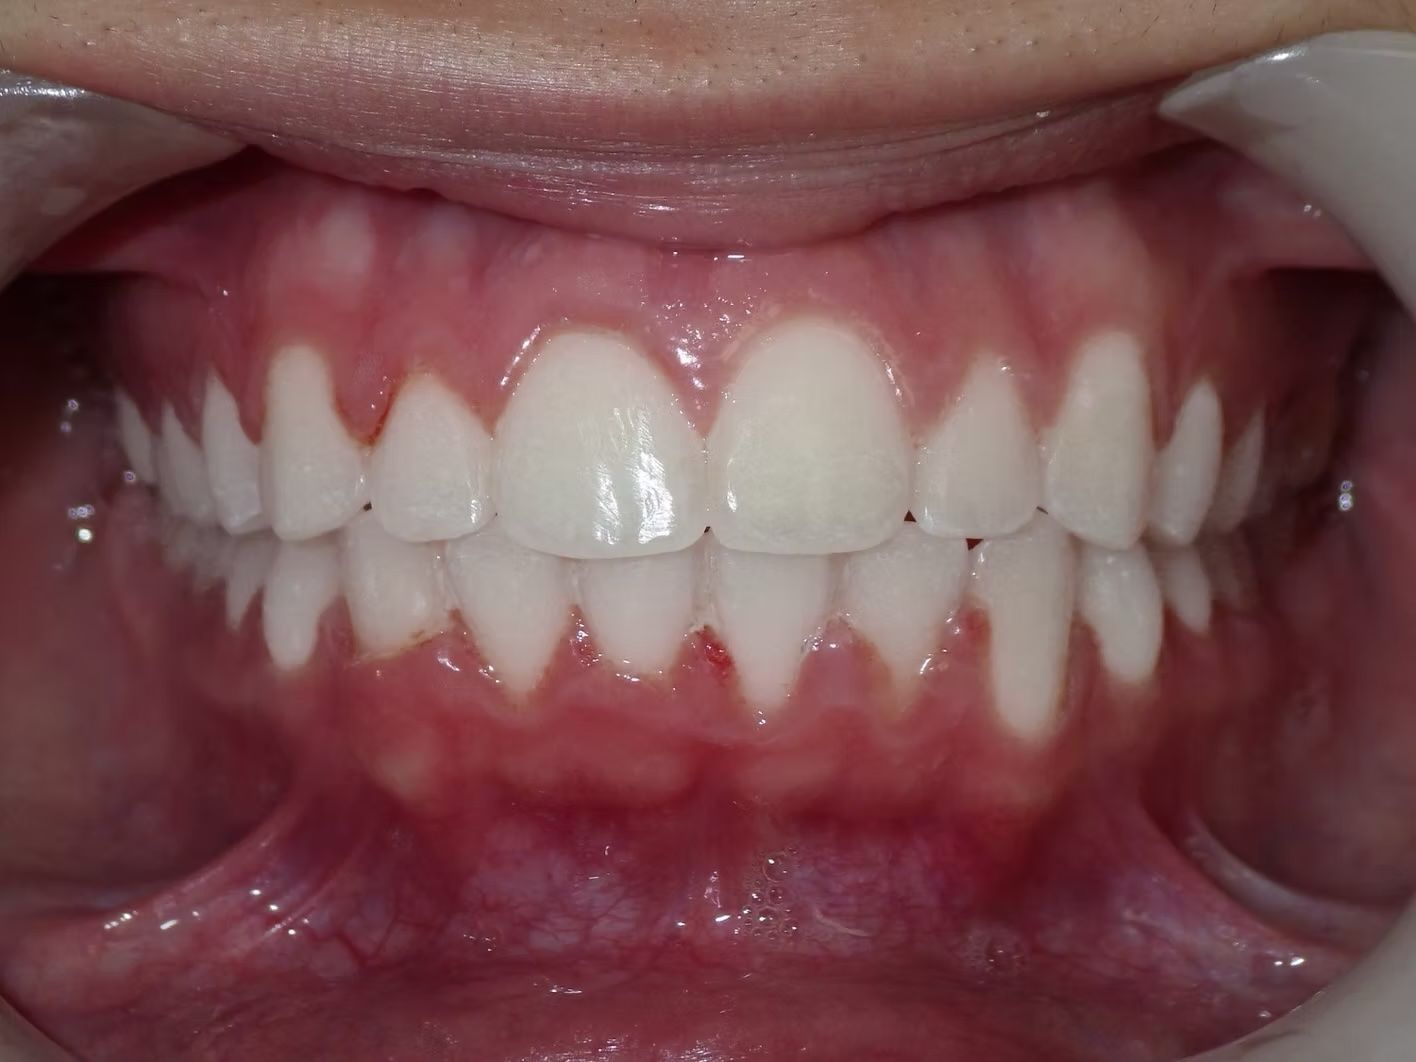

Emily

Emily didn't like how her top teeth were turned in and the lower teeth were crowded. Her bite was slightly off on both sides. Emily just needed upper and lower braces to correct her dental alignment and some rubber bands to correct the bite. She absolutely loves her teeth now!